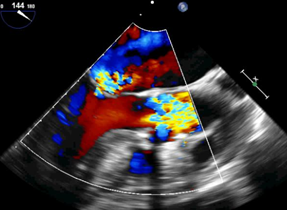

患者超声心动图:严重的主动脉瓣狭窄、二尖瓣返流

黄焕雷主任带领具有丰富经验的心脏麻醉医师、体外循环师、超声心动图医师、手术室、心外重症监护室、心脏导管室多学科团队,联合心内科专家谢年谨主任,为蔡先生实施小切口下、介入途径的主动脉瓣“瓣中瓣”、二尖瓣“环中瓣”的同期植入手术:黄主任首先在患者左前胸做一小切口,暴露患者的心尖,在跳动的心脏上“绣”上荷包作为介入导管、瓣膜的植入“门户”;随后,黄焕雷主任在超声心动图、放射透视的引导下,将一钢针在患者心尖“扎”入患者心脏内,为之后的瓣膜植入作为引导,具体来说就是将预先选择适合患者大小的生物瓣膜折叠、压缩入细长的输送管道内,好比将瓣膜这一“弹头”安放在输送导管这颗精准制导的“火箭”上,而黄主任的双手则控制这一精准发射和制导,再将瓣膜输送到主动脉合适的位置后释放,新的主动脉瓣便牢固地“卡”在了原有的主动脉瓣架内。经过透视和超声心动图评估,主动脉瓣位置合适,开放、闭合功能良好。随后,黄主任通过这一根钢针和输送导管,利用类似的方式,调整“火箭”的发射轨道,在原有二尖瓣人工瓣环内植入预先选择好大小的二尖瓣生物瓣膜,经过影像学方式评估,新植入的二尖瓣生物瓣工作良好。